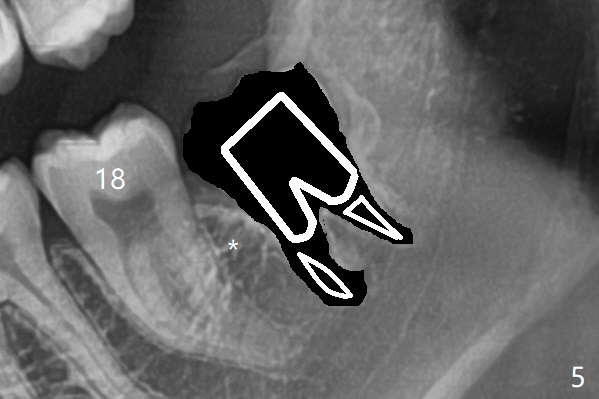

A 19-year-old man returns for #1,16,17 and 32 extraction (Fig.1,2). Because of horizontal impaction of #32 and no bone #31 distal post extraction (Fig.3 *), 3D bond (.5 cc) will be placed in the mesial socket of #32 (Fig.4 red), while Osteogen plug (1/2 (O)) in the distal one. Since there is no bony defect between #17 and 18 after extraction (Fig.5 *), a piece of Osteogen plug (cut half apical) will be inserted in #17 socket, whereas 2 small pieces of Osteogen plug placed in the apical portions (triangle and spindle shaped). Take posterior panoramic X-ray postop (bitewing type, CT format, not XV). There appears bone formation in the socket 5 months postop (Fig.10,11).

Since #32 sockets seem large, extending mesiobuccal (Fig.6), Bond Apatite (1 cc) is placed instead (Fig.7 B), covered by 1/3 of Osteogen plug (O) and sutured with 4-0 PGA. Extraction of #17 is also difficult. As 2 sockets are indistinct, a piece of Osteogen plug with split is placed (Fig.8) upside down (Fig.9 vs. Fig.5). There appears bone formation in the socket 5 months postop (Fig.10,11).